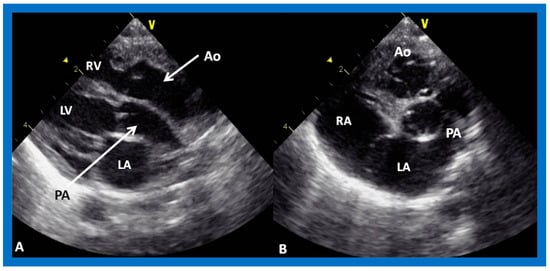

The relationship between the great arteries is characterized as 1. Normal, in which case, the aortic valve is placed inferior to, posterior to, and to the right side of the pulmonary valve (Figure 31 and Figure 46), 2. Transposed great arteries (d-TGA) with the aortic valve superior to, anterior to, and to the right side of the pulmonary valve (Figure 35, Figure 36 and Figure 47), or 3. Inverted (l-TGA) with the aortic valve superior to, anterior to, and to the left side of the pulmonary valve (Figure 40 and Figure 41). If the inter-relationship between the semilunar valves is abnormal but cannot be classified into one of the above groups, such abnormalities may be designated as malposition (d-malposition, l-malposition, AP-malposition).

Figure 46. Echo images in subcostal long-axis projections of the right (RV) (A) and left (LV) (B) ventricles illustrating the position of the pulmonary valve (PV). The PV is located higher and anterior to the aortic valve (AV). The AV is located on the right side of the PV in straight posteroanterior view (not shown in this illustration). As expected, the LV is seen posteriorly while the RV is anterior. Aorta (Ao) and pulmonary artery (PA) are labeled. Replicated from reference [41].

Figure 47. Echo images in parasternal long (A) and short (B) axis projections of a baby with transposition of the great vessels illustrating anterior (A,B) and right-ward (B) position of the aortic valve and aorta (Ao) relative to the position of the pulmonary valve and pulmonary artery (PA). These images also demonstrate that the PA and Ao are in parallel position (A). Left atrium (LA), left ventricle (LV), right atrium (RA), and right ventricle (RV) are labeled. Replicated from reference [42].